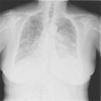

La aparición radiológica de múltiples micronódulos como forma de presentación de un tumor pulmonar aunque está descrita1, es muy infrecuente (fig. 1).

Presentamos el caso de una mujer de 71 años, nunca fumadora, sin alergias medicamentosas conocidas con antecedentes de HTA, hipotiroidismo yatrógeno, epilepsia y cirugía de resección de quistes ováricos. En tratamiento con levotiroxina, ácido valproico, omeprazol, captopril y diclofenaco. En situación basal no presentaba sintomatología respiratoria. Ingresa por cuadro de un mes de evolución de disnea progresiva hasta hacerse de mínimos esfuerzos, tos con escasa expectoración mucosa, sibilancias, dolor costal pleurítico bilateral y ortopnea de dos almohadas. Durante ese tiempo había recibido tratamientos con antibiótico y corticoides sin mejoría. No existían antecedentes de exposición laboral a humos ni ambientes pulverícenos. Tenía como mascota un perro. Desde hacía 4 meses un vecino había instalado un gallinero al lado de su domicilio (pared con pared). En la exploración física destaca saturación arterial de oxígeno basal del 80%, taquipneica al habla a 30rpm y crepitantes en zona posterior de hemotórax izquierdo que sólo respetan el vértice. En las pruebas complementarias a su ingreso destaca: leucocitosis: 1.1700/Ul con neutrofilia del 79%, y gasometría realizada con un aporte desconocido de O2: PaO2: 80mmHg; PCO2: 30mmHg; pH: 7,52; HCO3−: 26mEq; SaO2: 97%. En la radiografía de tórax se observaba un patrón alveolointersticial difuso con tendencia a confluir. En la TAC torácica se apreciaban numerosos micromódulos repartidos de forma aleatoria por la totalidad del parénquima pulmonar con áreas parcheadas confluyentes condensatorias de tipo algodonoso alveolar que se acompañan de derrame pleural derecho leve y moderado izquierdo así como escasas adenopatías mediastínicas en el límite, poco significativas. Durante su ingreso además se realizan otros estudios que incluyeron: toracocentesis diagnostica observándose exudado linfocítico cuya citología era inespecífica; serología con hallazgo de Ig G frente a Coxiella 1/160 con IgM negativa; estudio de esputo donde se aísla Candida albicans (posible contaminación orofaríngea), baciloscopias negativas; marcadores tumorales con elevación de CA 15.3, CA 125 y CEA; enzima convertidora de angiotensina con valores normales; mamografía, donde se observa nódulo de 9mm en mama derecha de probable origen benigno y del que se recomendaba control en 6 meses; examen ginecológico que descarta patología ginecológica; precipitinas frente a suero de gallinas negativas, fibrobroncoscopia donde sólo cabe destacar mucosa de bronquio principal izquierdo de apariencia rugosa sin signos de infiltrado ni masas endobronquiales. PET: lesiones hipermetabólicas en ambos parénquimas pulmonares, ganglios mediastínicos, ganglio infradiafragmático, pleura, hueso y más dudosamente ganglios laterocervicales, altamente sospechosos de malignidad sin poder descartar por completo etiología infecciosa (tuberculosis).

Aunque la presentación radiográfica de un tumor pulmonar como patrón micronodular está descrita1, es muy infrecuente y a menudo, difícil de interpretar. Sí están descritos casos de presentación de un tumor pulmonar, como opacidades en vidrio esmerilado2,3, que pueden observarse en el carcinoma bronquioloalveolar y el adenocarcinoma, pero también esta forma de presentación es infrecuente3. En este caso, la anatomía patológica nos informa de un adenocarcinoma de probable origen pulmonar. Dado que no se realizó autopsia, no es posible afirmarlo con certeza, sin embargo, las pruebas complementarias realizadas no encontraron evidencias de tumores primarios en otros órganos. Esto coincide con los resultados del estudio realizado por Al-Brahim4 en el que se halló que el adenocarcinoma es el tumor que más frecuentemente se presenta con metástasis múltiples y que las localizaciones del tumor primario más frecuentes eran el pulmón en primer lugar y en segundo lugar el intestino grueso.